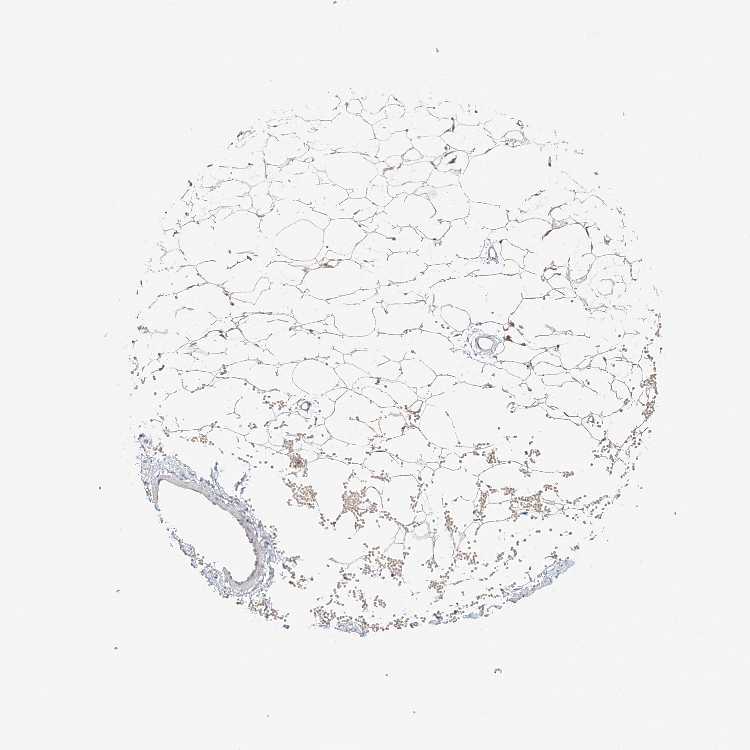

SOFT TISSUE 1 - Antibody stainingi

Antibody staining in the annotated cell types in the current human tissue is reported as not detected, low, medium, or high, based on conventional immunohistochemistry profiling in selected tissues. This score is based on the combination of the staining intensity and fraction of stained cells.

Each image is clickable and will lead to virtual microscopy that enables deeper exploration of all samples and also displays staining intensity scores, fraction scores and subcellular localization as well as patient and tissue information for each sample.

Antibody HPA008455Antibody HPA031125Antibody CAB002781

Chondrocytes Not detectedNot detectedMedium

Fibroblasts Not detectedLow-

Peripheral nerve Not detectedNot detected-